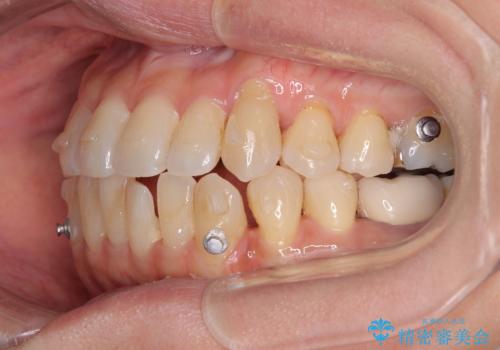

- インビザライン

受け口傾向の骨格であり、前歯はクロスバイトまたは切端咬合となっており、下顎を中心に歯列全体の後方移動を行い、IPR(歯と歯の間を削る)によってデコボコが解消するように設計し、インビザラインにより治療を行うこととしました。

受け口傾向のインビザライン矯正は比較的治療を行いやすいため、きれいに仕上げることができました。舌の突出癖が顕著であったため、改善のためのトレーニングをしっかりと行っていただきました。